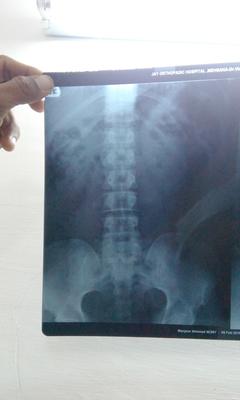

dorsal x ray

I am 29 years old. From the last one month I am having continous pain in my back. First I thought it might be muscular pain. Later I consulted Orthopaedic surgeon who diagnosed me with decreased space L4-5-S1. Plz help me what treatment should I take?

It appears that you may have six lumbar vertebrae instead of five, sometimes creating abnormal joints at the sacrum.